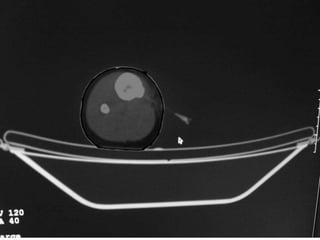

• Excision of the osteoid osteoma nidus using

CT–assisted localization, a Kirschner wire

inserted into the nidus, and a biopsy punch

inserted over the Kirschner wire into the

bone.

• They recommend using a trephine 2 mm

larger than the lesion for complete removal.

CT – Guided Drilling

•

OPD procedure,

Localization of the nidus in CT Scan,

Local anesthesia,

K-wire passed into nidus,

Transferred to OT,

Short GA,

Drilling of the nidus by a cannulated drill,

Complete relief of pain.